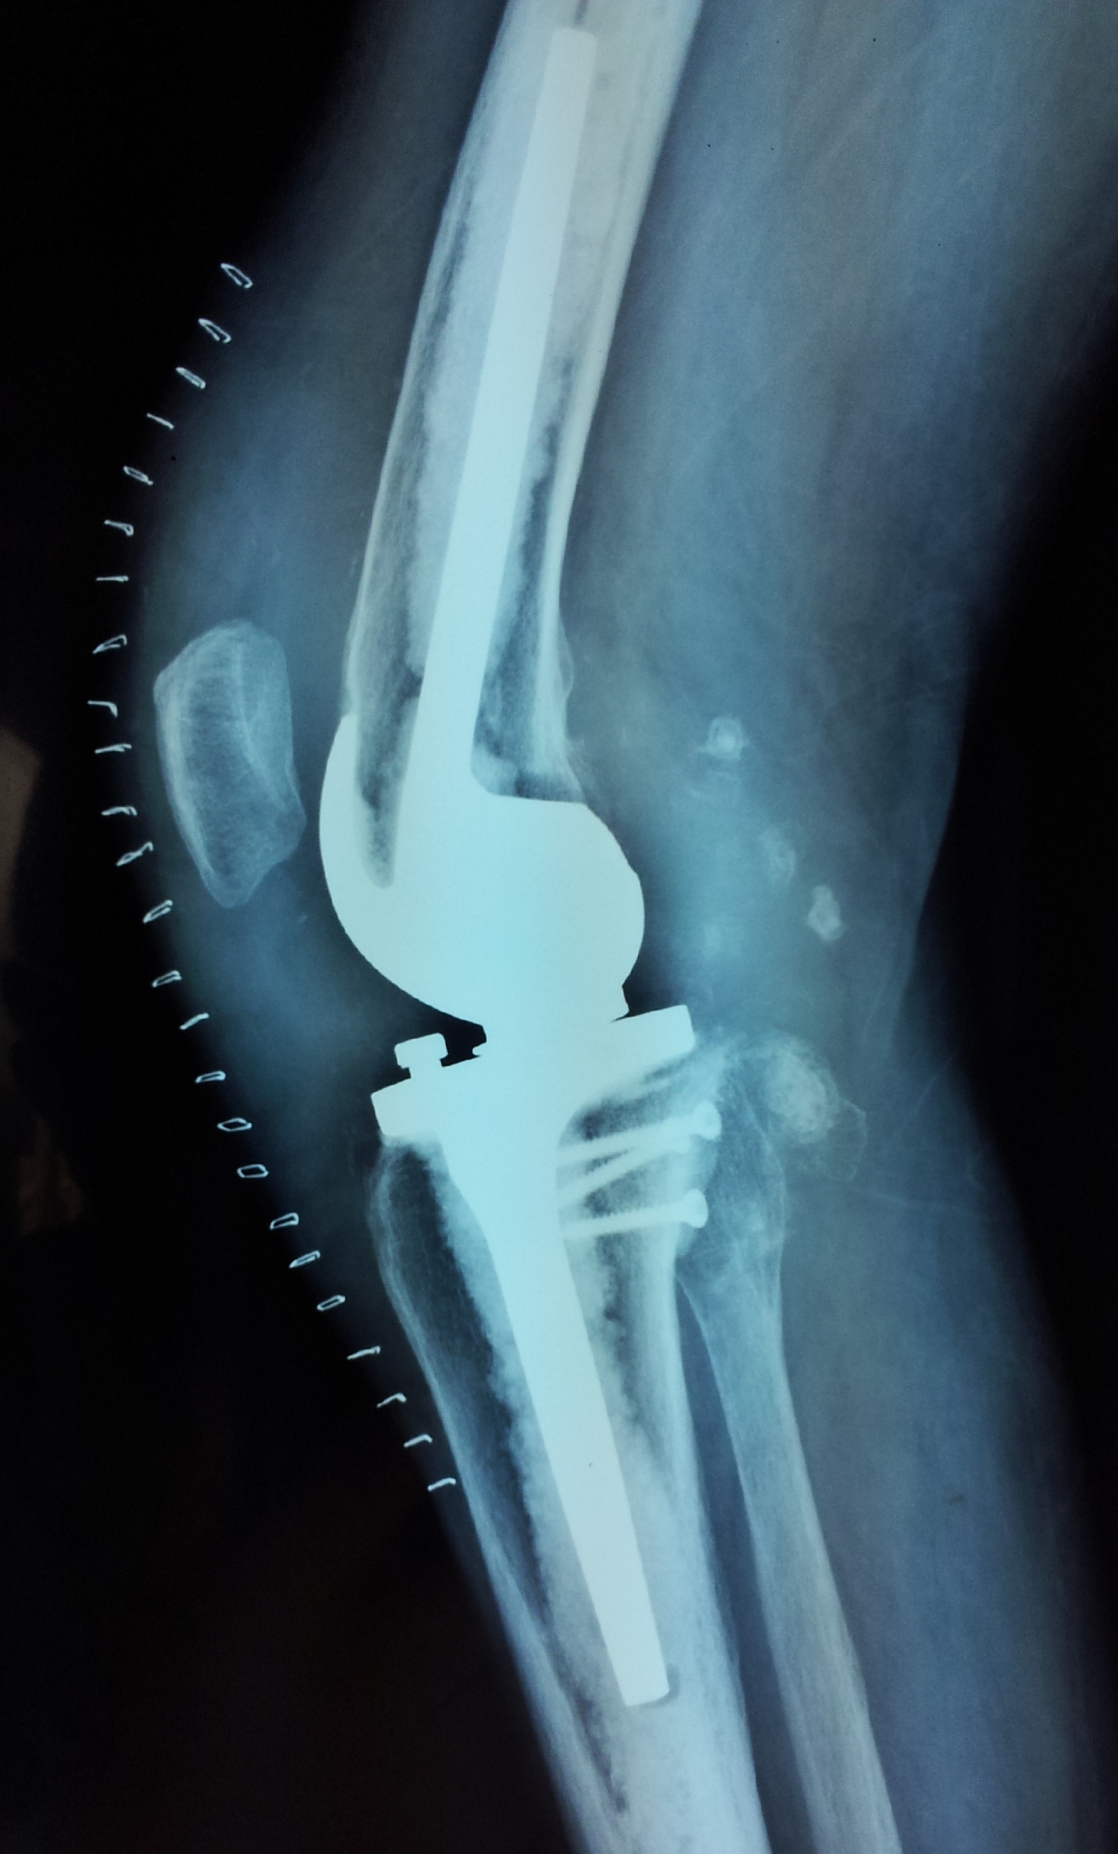

典型病例:患者,女,60岁,右膝骨性关节炎(重度内翻畸形)

术前                           术后

术前  侧位                         术后侧位